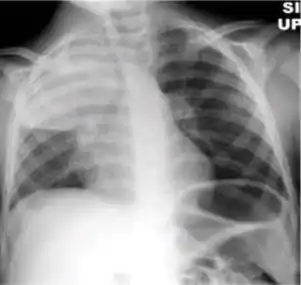

2. Any cavitary lesion - Lucency (darkened area) within the lung parenchyma, with or without irregular margins that might be surrounded by an area of airspace consolidation or infiltrates, or by nodular or fibrotic (reticular) densities, or both. The walls surrounding the lucent area can be thick or thin. Calcification can exist around a cavity.

Chest X-ray of a person with advanced tuberculosis: Infection in both lungs is marked by white arrow-heads, and the formation of a cavity is marked by black arrows.